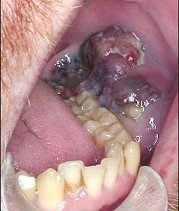

男性患者,50岁,发现口内粘膜黑色肿物两年,近期生长迅速,且破溃,出血,伴疼痛,有颌下淋巴肿大。外观如图示。最可能的诊断为()

A.海绵状血管瘤

B.复发性溃疡

C.舌下腺囊肿

D.恶性黑色素瘤

E.颊粘膜癌